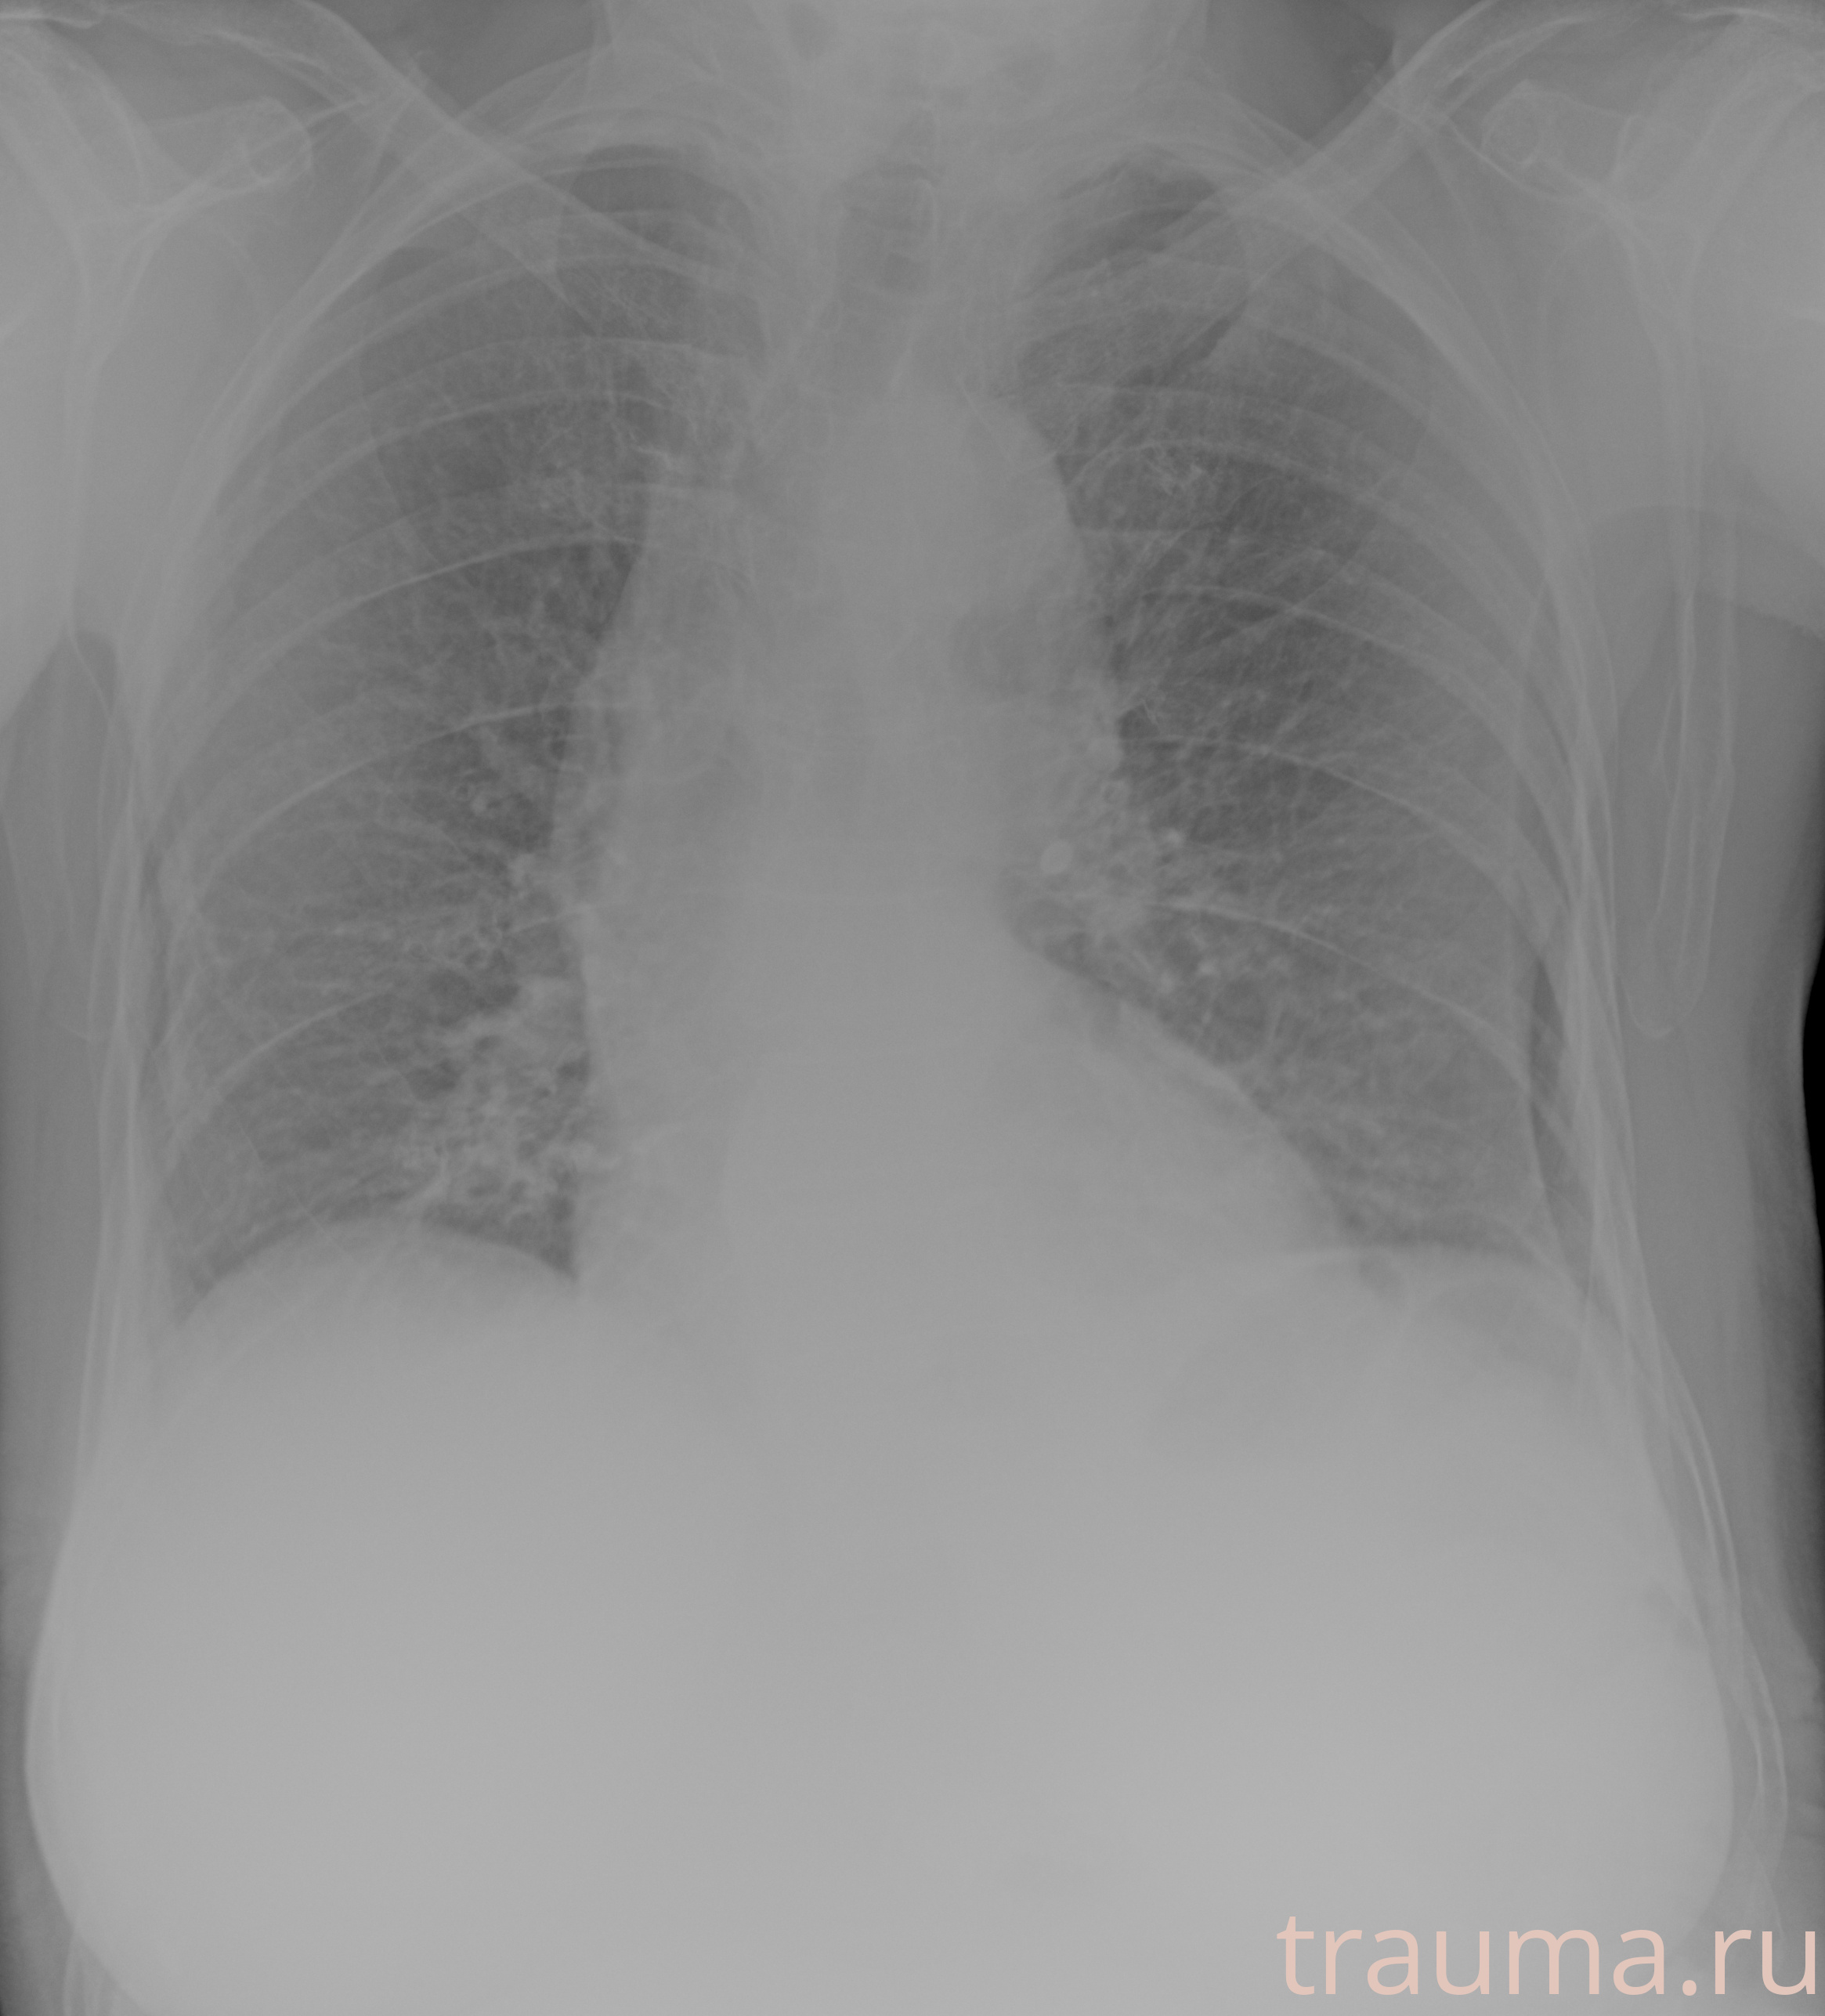

Рентгенограммы

Рентген на дому: по вашему адресу приезжает врач-рентгенолог, травматолог-ортопед с мобильным рентгеновским аппаратом, проводит диагностику травмы или заболевания, делает необходимые рентгенограммы, дает рекомендации по дальнейшему лечению. Получить качественные снимки в домашних условиях возможно благодаря уникальной методике, разработанной МосРентген Центром для института  Склифосовского

при переломе шейки бедра и пневмонии от компании МосРентген Центр - партнера Института имени Склифосовского